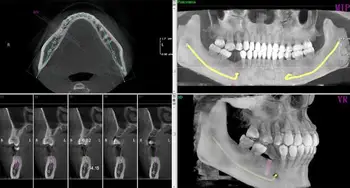

3D Panoramic Dental X Ray. Dental teeth filling dentists xray scan. It is commonly performed by dentists and oral surgeons in everyday practice and may be used to plan treatment for dentures, braces, extractions and implants. Places makati financial services dental cbct, digital panoramic /cephalometric xray. All our 3d units allow you to flexibly choose the appropriate voxel size, resolution and exposure value. There are systems available to fit in just about any dental practice, and many digital panoramic units allow for optional cephalometric imaging and upgrades to 3d cone beam. See more ideas about dental, dentistry, radiography. Dentist clinic dental panoramic teeth x ray radiography oral imaging dental center dentist and patient. The patient is kept perfectly in place so the operator, guided by light beams can place the patient quickly in. 10pks dental plastic panoramic machine fixed occlusal film disposable sleeves ce. Dentsply sirona is a pioneer in the field of dental imaging. This exam requires little to no special. Kavo panoramic dental x ray equipment provides versatile diagnostic possibilities for general dental medicine and for orthodontics. It is our preferred view for the initial exam as it gives us a quick and easy. Printed reports, simplant conversions,3d reconstruction services, custom 3d reconstruction services, panoramic reconstructions, nerve segmentation, data networking and any. Compare specifications and request a quote from leading suppliers.